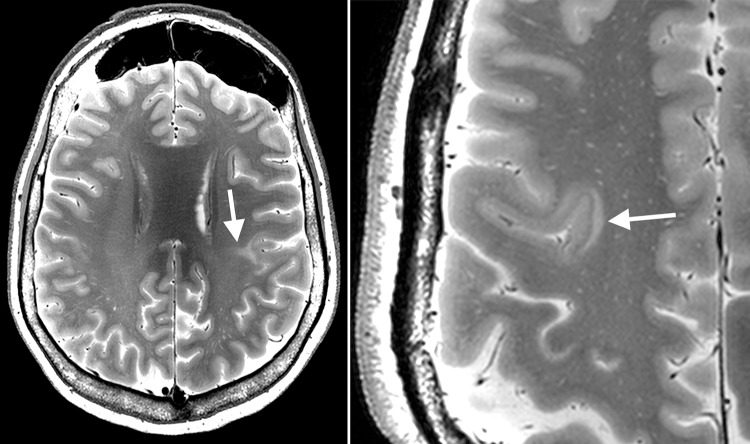

Fig. 2.

7 T T2 image showing cortical thickning, transmantle sign (left) and flag-like appearence at the bottom of the sulcus in FCD (right more pronounced than left)